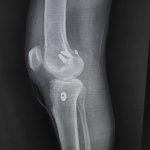

Orthopaedic Surgeon | Arthroscopy & Joint Replacement Specialist

Dr. Aditya Tripathi is a dedicated and skilled Orthopaedic Surgeon specializing in sports injuries, arthroscopy, and joint care. Known for his clinical precision, ethical practice, and patient-first approach, he focuses on helping patients regain mobility, strength, and confidence through evidence-based orthopaedic treatment. His academic background and hands-on clinical training reflect a strong foundation and a commitment to excellence in orthopaedic care.

Dr. Aditya Tripathi is widely appreciated by patients for his clear communication, honest medical guidance, and personalized treatment approach. His expertise in managing ACL tears, ligament injuries, shoulder conditions, and sports-related injuries makes him a trusted choice for comprehensive orthopaedic and sports injury care. Patients value his attention to detail, compassionate care, and focus on long-term recovery—establishing him as a reliable and respected orthopaedic specialist.

- Arthroscopy-Knee

- Knee Replacement Surgery